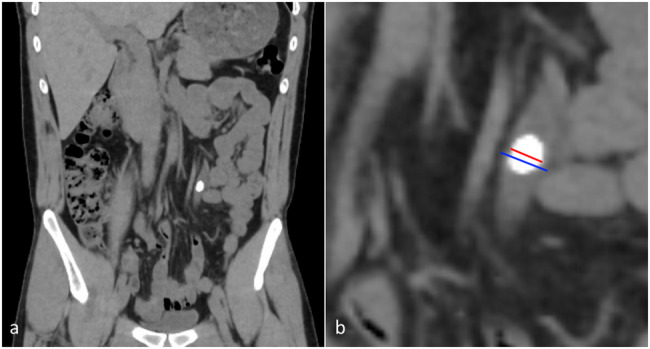

Methods: Data of patients over the age of 18 years who underwent URS-L for a single ureteral stone were prospectively collected. First, stone impaction was determined by the primary surgeon using a Likert scale. Subsequently, non-impacted and impacted stones were further divided into two subgroups and classified according to the degree of stone impaction between Grades 1 and 4. Patient characteristics, preoperative non-contrast computed tomography (CT) findings, laboratory values, and intraoperative and postoperative outcomes were analyzed. Stone-free status was defined as the absence of residual stones > 2 mm on non-contrast CT at postoperative month 1.